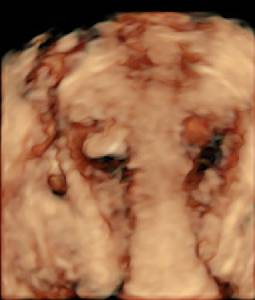

Abb. 2

Der 3‑D-Ultraschall des Uterus aus Abb. 1 zeigt die auffallend kugelige Form, die das Organ bei Adenomyose häufig aufweist